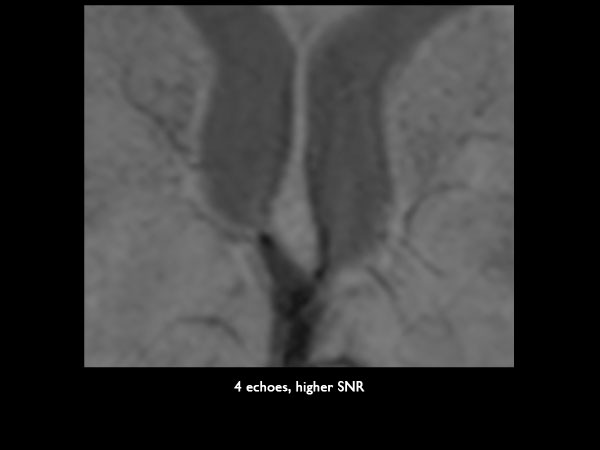

Axial 3D SWIp